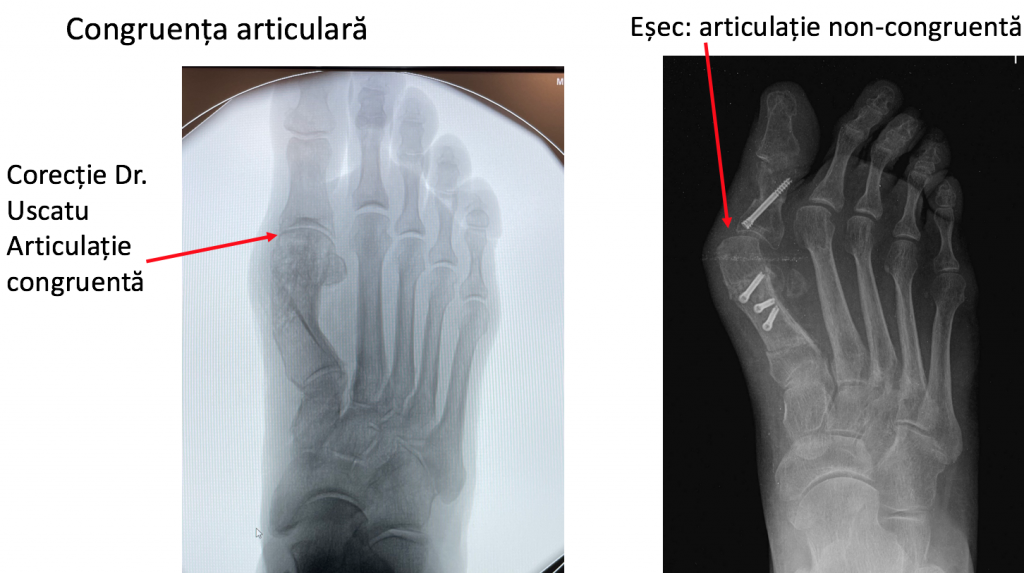

- articulatia "degetului mare" este incongruenta si functioneaza excentric (asimetric); functionarea defectuoasa a articulatiei conduce la distrugerea ei progresiva (hallux rigidus), printr-un proces de uzura de tip mecanic (artroza).

- corectia deformatiei presupune schimbarea pozitiei osului deplasat catre pozitia sa initiala: primul metatarsian trebuie re-aliniat (re-axat) cu halucele ("degetul mare");

- practic, primul metatarsian se sectioneaza complet longitudinal, fragmentele osoase obtinute se translateaza unul fata de celalalt, iar partea distala a osului se re-pozitioneaza la locul sau initial, pe "soclul" sesamoidian;